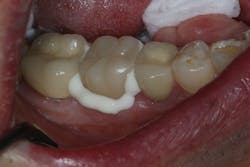

TheraCem exhibits minimal resistance to seating, but is not runny (figure 3). Cleanup is easy with hand instruments and floss (figure 4). For deeper subgingival margins, this cement is kind to the gingiva, although the margins should be thoroughly inspected to ensure complete removal of excess cement (figure 5).

Figure 3: TheraCem in use